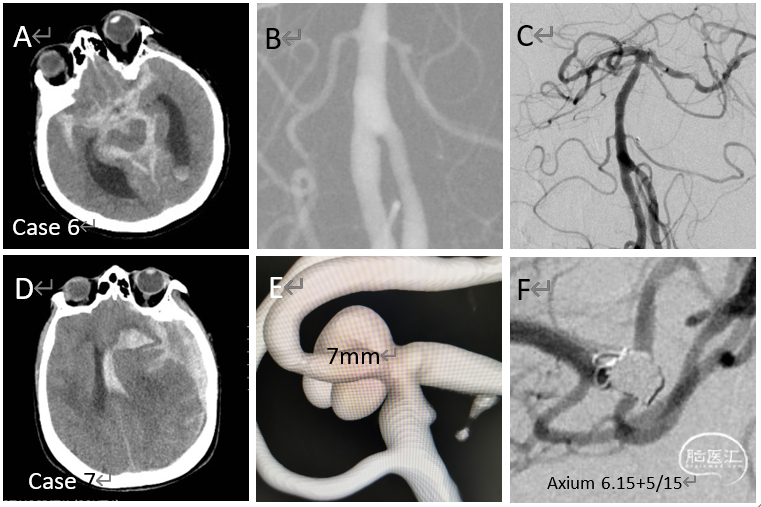

病例6-7

破裂的小脑前下动脉起始部动脉瘤

(Hunt-Hess 5级,Case 6)

破裂的左侧大脑中动脉分叉部动脉瘤

(Hunt-Hess 5级, Case 7)

急性期给予单纯栓塞,接着分别进行脑室外引流(Case6)和颅内血肿清除+去骨瓣减压术(Case7)